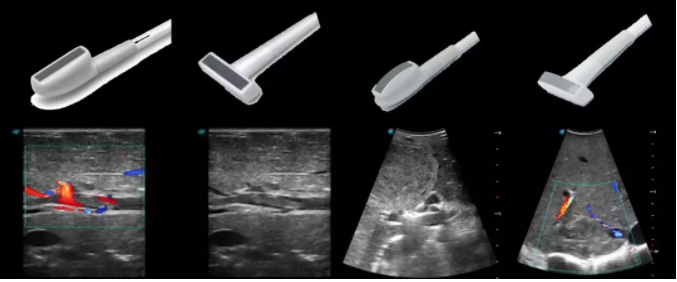

6多種指夾式探頭

線陣/凸陣不同選擇,多種外形設(shè)計(jì)可以滿足適用于不同的臨床科室,滿足不同醫(yī)生的使用需求;

輕便小巧,方便持握;

防水、易消毒;

應(yīng)用科室:手術(shù)室、肝膽外科、消化外科、腫瘤科、心胸外科、泌尿外科、婦產(chǎn)科等